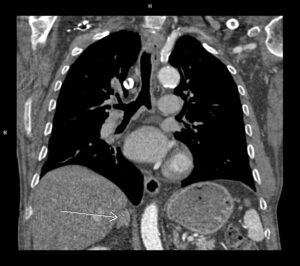

Discuţie caz nr 46: Sindromul Alagille (cunoscut și sub numele de displazie arteriohepatică) este o afecțiune genetică multisistem congenitală sau dobândită cu modificări diverse: hepatice, renale, oculare, otice, scheletale, faciale şi cardio-vasculare. Manifestările cardio-vasculare sunt coarctaţia de aortă şi stenoze vasculare.

Este cazul unei paciente de 24 de ani cu un părinte cunoscut cu Sd Alagille care se prezinta la camera de gardă pentru cefalalgii importante. Examinarea angioCT a evidentiat ocluzie de artera carotidă internă stângă la origine şi a fost completată cu examinare IRM pentru diagnostic diferențial cu disecție de perete vascular.